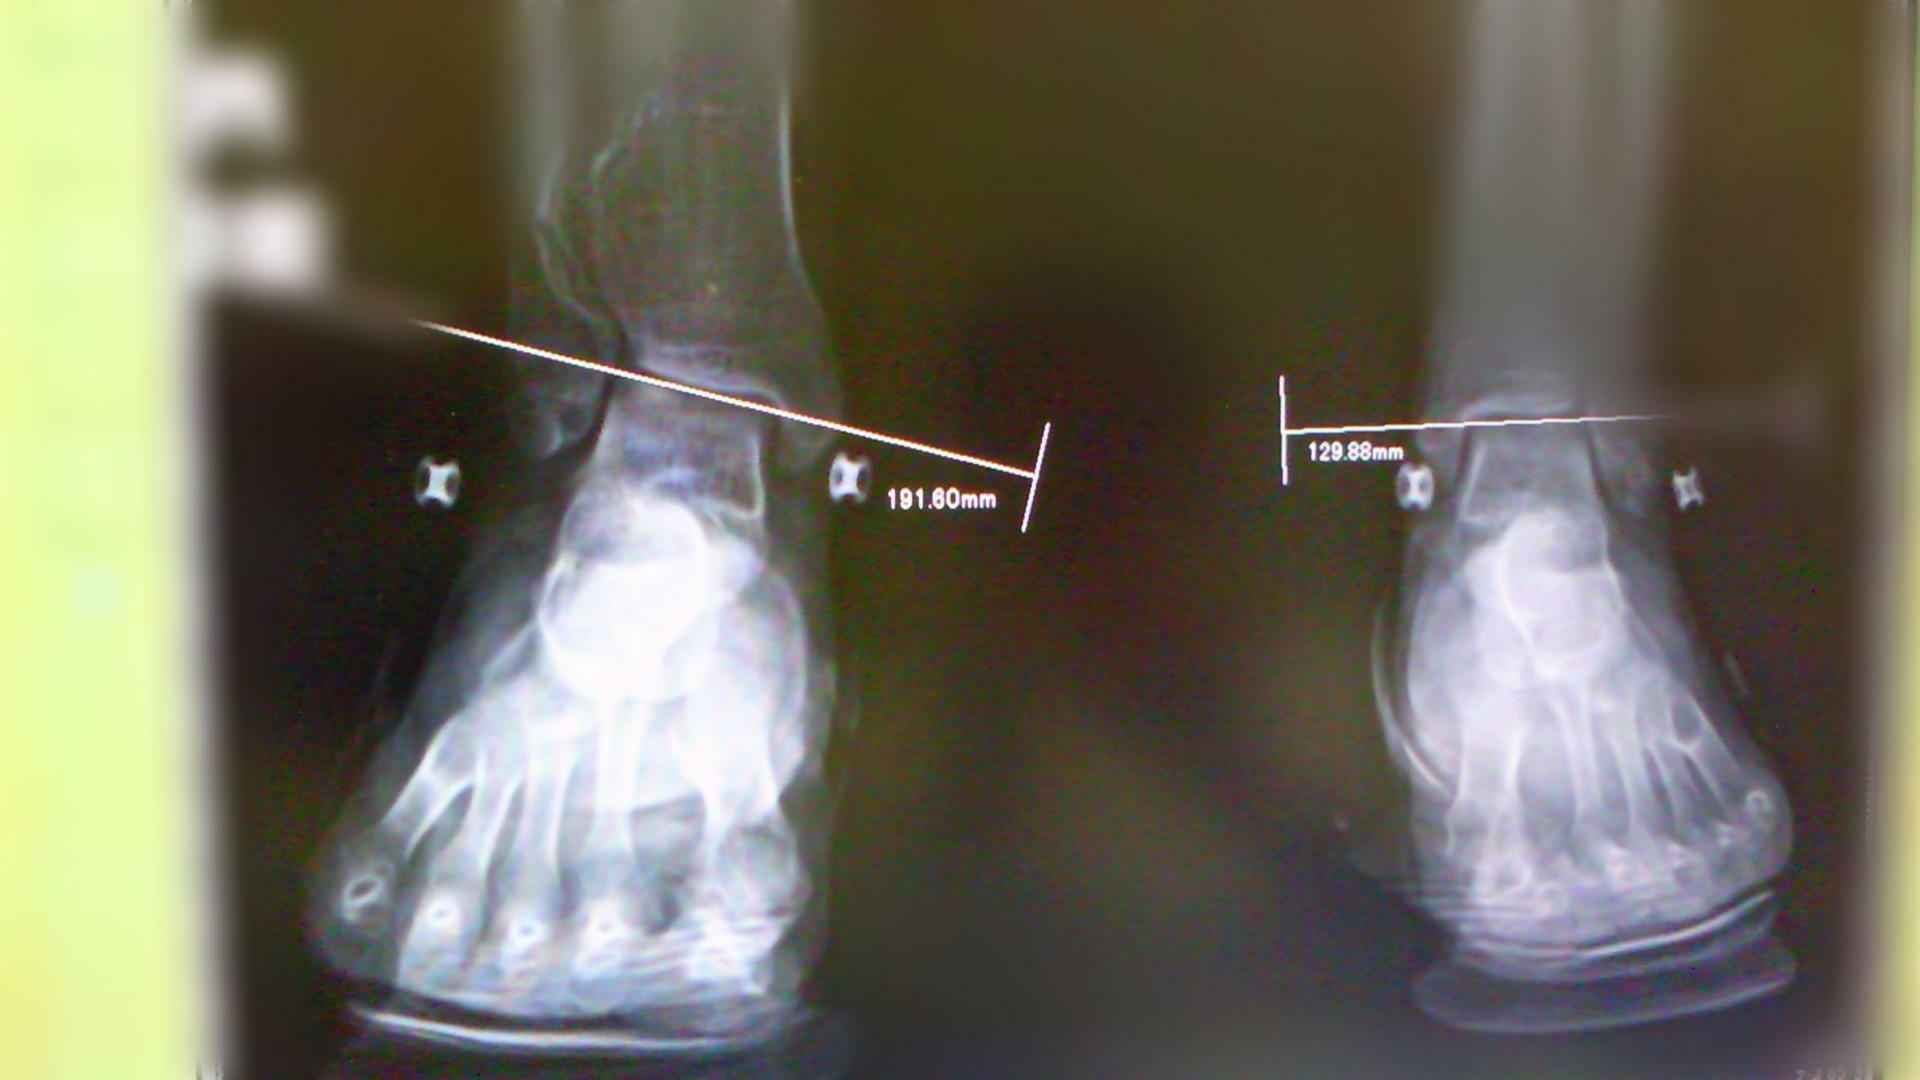

久々の来店で、足のアーチのチェックをしてみたところなんとアーチが高くなっていた